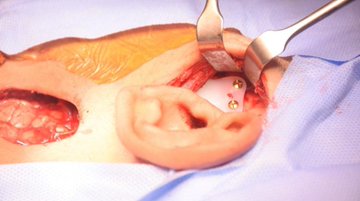

تمكَّن فريق طبي جراحي في جراحة الوجه والفكين في كلية طب الأسنان ومستشفى طب الأسنان الجامعي في المدينة الطبية بجامعة الملك سعود و للمرة الثانية -بحمد الله- من إجراء عملية جراحية للاستعاضة الاصطناعية للأذن من خلال زرعات لمريض في السابعة عشر من عمره تم تشخيصه بعيب خلقي في الأذن اليمنى.

وقد اعتمد الفريق خطة جراحية من خلال ازالة التصلب العظمي في المفصل وقاع الجمجمه، وتعويضه بمفصل صناعي، صمم وصنع خصيصا باستخدام التخطيط الجراحي الافتراضي، ثلاثي الابعاد.